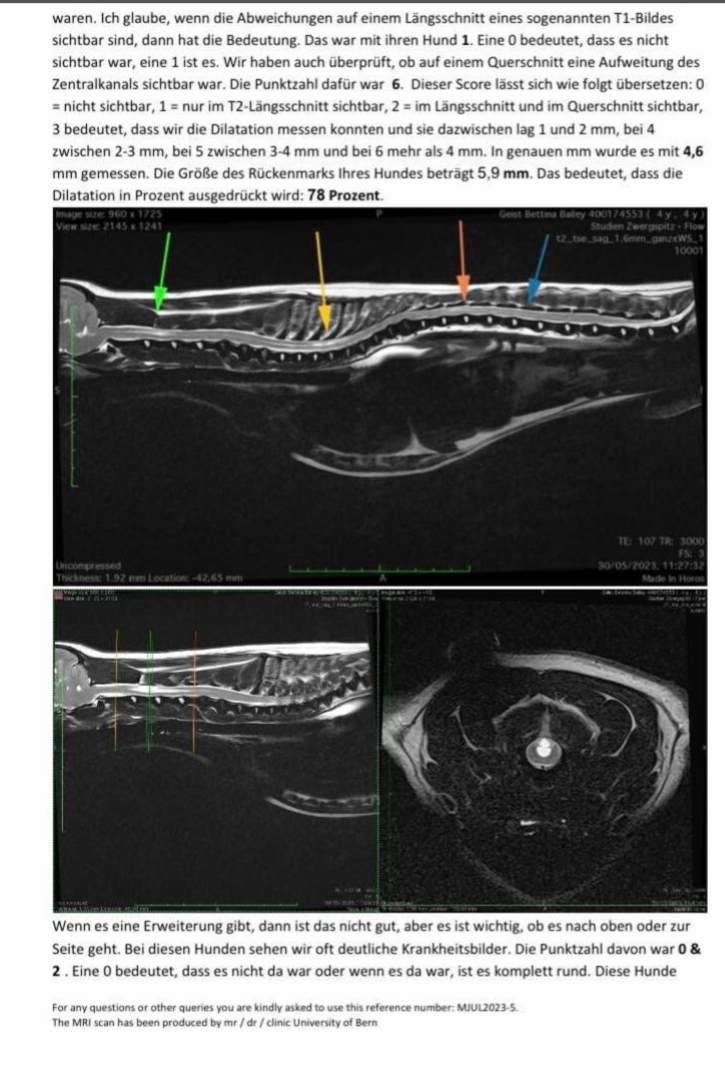

Relativ schnell mussten wir mit ihm zum Tierarzt aufgrund seiner Augen. Da der Tierarzt nicht weiter wusste, schickte er uns zum Spezialisten. Dort wurde festgestellt er hat eine Kerastitis superficialis chronica hat. Leider ist das nicht Heilfasten, da es eine autoimmune Erkrankung ist. Er bekommt täglich spezielle Tropfen und am schlimmeren Tagen noch Kortisontropfen. Ausserdem haben wir in Mai an einer Studie teilgenommen und da wurde noch CM grad 2 und SM grad 2 festgestellt. Er hatte nie irgendwelche Symptome und ist ein super sportlicher Hund. Umso überraschter waren wir von seiner schlimmen Diagnose. Dazu kommt noch eine verkümmerte Wirbelsäule. Ein überbiss und sehr schlechte Zähne.